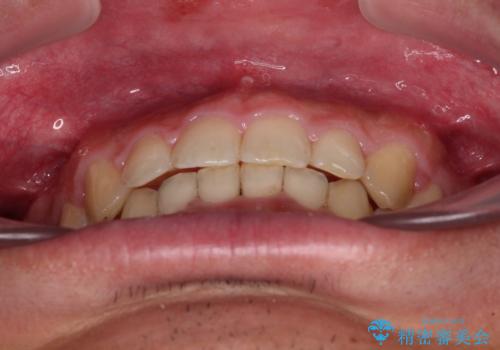

深い咬み合わせと隙間の空いた歯列をワイヤー矯正で改善

- 前歯の隙間と深い咬み合わせを改善したいとのことで来院された患者様です。

奥歯の咬み合わせは理想的な状態であったため、ワイヤー矯正でもインビザラインでも比較的容易に対応可能でした。